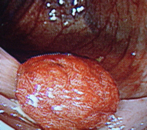

良性の胃ポリープと異なり、大腸ポリープはたとえ現在良性でも将来癌化する可能性があることが知られています。したがってある程度の大きさのポリープは切除することをお勧めします。当院では日帰りで可能ですが

「内視鏡下でポリープ切除が可能」とは言っても、これは手術に該当するものであり、大腸穿孔や術後出血などを引き起こす可能性があります。ポリープを切除した傷が完治するまでの2〜3週間は、食事制限、運動制限、禁酒など合併症予防のために遵守すべき事項があるので、手術を受ける際は厳守して下さい